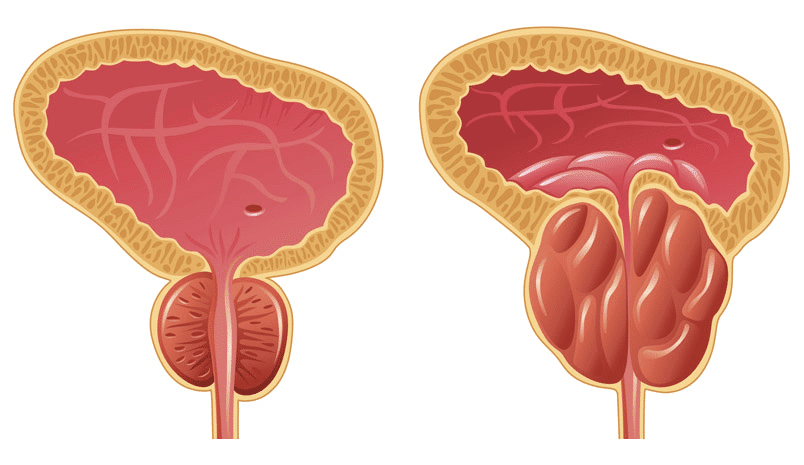

῾Η ὑπερπλασία τοῦ προστάτη προσβάλλει τό 50% τῶν ἀνδρῶν μέσης ἠλικίας. ῾Η διόγκωση χωρίς ἀπόφραξη τῆς οὐρήθρας δέν συνιστᾶ πρόβλημα . ῾Η ἀπόφραξη τῆς οὐρήθρας εἶναι ἡ γεννεσιουργός αἰτία τοῦ προβλήματος μέ ἀποτέλεσμα εἴτε πιό ἀργή ροή οὔρων εἴτε διακοπές κατά τήν οὔρηση. ῾Η κατάσταση αὐτή προϊόντος τοῦ χρόνου μπορεῖ νά δημιουργήση προβλήματα καί στούς νεφρούς.